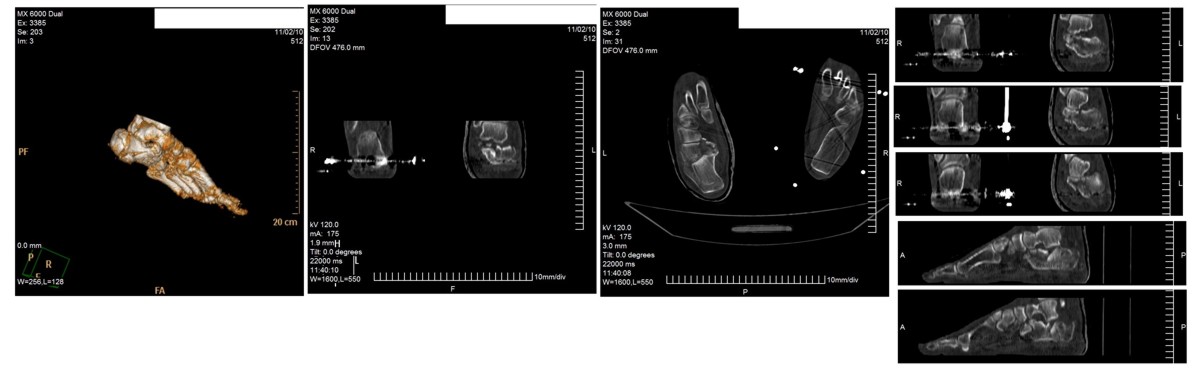

Уважаемые коллеги!Мужчина, 47 лет. Диагноз: Кататравма (26.10.10г. падение с высоты 2го этажа). Открытый оскольчатый внутрисуставной перелом дистального метаэпифиза лучевой кости, перелом шиловидного отростка локтевой кости левого предплечья со смещением отломков, закрытый оскольчатый внутрисуставной перелом дистального метаэпифиза лучевой кости, перелом шиловидного отростка локтевой кости правого предплечья со смещением отломков. Закрытый оскольчатый внутрисуставной перелом левой пяточной кости, закрытый оскольчатый внутрисуставной перелом дистального метаэпифиза обеих костей правой голени со смещением отломков, закрытый компрессионно-оскольчатый перелом тела L2 позвонка с болевым вертеброгенным синдромом. 						Голень и предплечья синтезированы АВФ в ургентном порядке. В настоящее время состояние пациента стабильное, к оперативному лечению соматически готов.		Во время клинического разбора мнения разделились: 1) открытая репозиция, МОС пяточной пластиной 2) гипсовая иммобилизация 3) ЧКО аппаратом внешней фиксации как репозиционный и окончательный вариант остеосинтеза. 4) необходимость СКТ? 	Коллеги, пожалуйста, интересует ваше мнение относительно тактики лечения,  необходимого перечня рентгенологического обследования оскольчатого внутрисуставного перелома пяточной кости и сроков выполнения предполагаемой операции. Просим высказаться относительно необходимости выполнения СКТ как важного этапа диагностики. Пациент будет повторно представлен на ближайшем клиническом разборе  (приветствуются примеры аналогичных клинических случаев, ссылки на современную литературу и диссертационные работы).Заранее благодарим!С уважением,А.В.ВладзимирскийДНИИТО